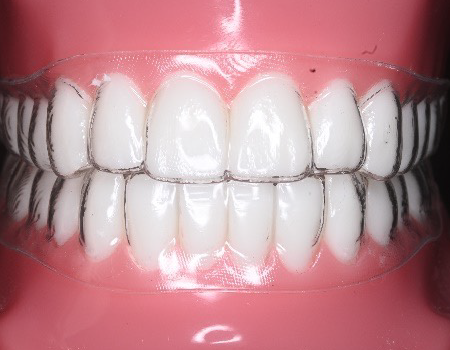

診療案内 medical information ホーム 診療案内 当院の治療のご案内 虫歯治療なるべく虫歯以外の部分を削らないようにし、患者様にも確認してもらいながら治療を進めます。もっと見る 予防歯科 (PMTC) 虫歯の早期発見のためにも当院は定期的な予防歯科をおすすめしております。もっと見る 小児歯科小児歯科は、成長発達期にある子どもの歯および顎や口を管理し、発育を助けるための医療です。もっと見る セレック即日で治療を行います。天然歯に近い美しいセラミックで、きれいに治療します。もっと見る 審美歯科虫歯治療をはじめ、気になっている箇所を美しく治療します。もっと見る ホワイトニング歯を削らずにスピーディーに歯を白くします。治療回数は3回となっております。もっと見る 歯周病治療歯茎が下がってきたり、口臭が気になる方に検査を受けていただき、最適な治療を行います。もっと見る インプラントインプラントをいれたその日からご飯が食べられます。入れ歯が合わない方もご相談ください。もっと見る デンチャー(入れ歯)60年の伝統に裏打ちされた治療を行います。もっと見る 訪問診療ご自宅や、施設まで診療に伺います。もっと見る 根管治療(歯の根の治療)再発がなるべく起こらない治療を目指しています。もっと見る かぶせ物やつめものの再発を少なくするために大切な身体の一部である歯を、可能な限り残す治療に取り組みます。もっと見る 親知らず抜歯大学病院に勤務しているDrによる親知らず抜歯を行っております。もっと見る 歯の移植歯がなくなった場合、インプラント、ブリッジ、入れ歯以外に、第4の選択肢として、歯の再植というものがあるのはご存じですか?もっと見る 有病者歯科ご病気のある方、基礎疾患、既往のある方の歯科治療。もっと見る 子供や大人の歯と口のケガ(外傷)当院では、近在教育機関の校医を行っており、長年歯や口のケガをした方の対応をしております。もっと見る マタニティ歯科これから妊娠をお考えや、妊娠中の方で、お口の中のトラブルひいては胎児への影響を少なくするために努めていきます。もっと見る セラミック、かぶせもの、詰め物の治療機能性にも審美性にもこだわる、調和のとれた審美治療を行います。もっと見る 矯正治療 歯並び 不正咬合部分矯正、ワイヤー矯正、マウスピース矯正、マウスピース矯正とワイヤー矯正を組み合わせて行うコンビネーション矯正治療が可能です。もっと見る 鎮静による治療法、当院が行っている痛みの少ない治療への取り組み、歯科集中治療のご提案無痛治療とまではいかないまでも極力痛みを少なくした状態で歯科治療を目指す方法として鎮静法があります。もっと見る 顎関節治療、歯ぎしり、噛みしめの治療顎関節症の原因は、様々な因子が関係しているといわれております。当院は大学病院口腔外科にて幅広く研鑽をつんだ副院長が、顎関節治療を行っております。もっと見る